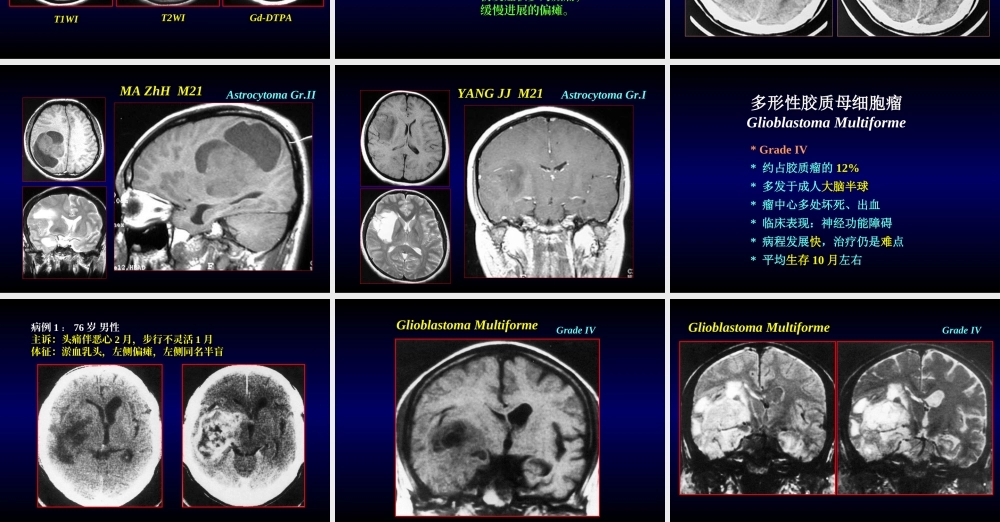

颅脑肿瘤与颅脑先天畸形IntracranialtumorsandCongenitalmalformations神经外科李瑞岩颅内肿瘤颅内肿瘤*原发性颅内肿瘤占全身肿瘤的2%,儿童为7%*男性多于女性*各年龄组均可发生(2岁以下和60岁以上少见)*原发性颅内肿瘤占全身肿瘤的2%,儿童为7%*男性多于女性*各年龄组均可发生(2岁以下和60岁以上少见)生长形式:生长形式:1扩张性生长2浸润性生长3多灶性生长1扩张性生长2浸润性生长3多灶性生长压迫脑组织脑的破坏多灶性症状压迫脑组织脑的破坏多灶性症状引起症状类型:引起症状类型:1颅内压增高症状2局灶性症状1颅内压增高症状2局灶性症状概述(1)概述(1)A.神经上皮组织肿瘤B.脑脊膜肿瘤C.颅神经和脊神经肿瘤D.造血系统来源的肿瘤E.生殖细胞肿瘤F.囊肿及肿瘤样病变G.鞍区肿瘤H.邻近肿瘤的局部扩张I.转移性肿瘤颅脑肿瘤(WHO)脑内神经细胞瘤(颞叶-基底核)室管膜瘤(脑室)脉络丛乳头状瘤海绵状母细胞瘤血管母细胞瘤星形胶质细胞瘤(单一形)少突胶质细胞瘤(单一形)室管膜瘤(大脑,脑室旁)神经细胞瘤(一般)神经细胞瘤(多形性)室管膜瘤(多形性)脉络丛乳头状瘤(多形性)星形胶质细胞瘤(多形性)少突胶质细胞瘤(多形性)胶质母细胞瘤髓母细胞瘤脑内神经细胞瘤(颞叶-基底核)室管膜瘤(脑室)脉络丛乳头状瘤海绵状母细胞瘤血管母细胞瘤星形胶质细胞瘤(单一形)少突胶质细胞瘤(单一形)室管膜瘤(大脑,脑室旁)神经细胞瘤(一般)神经细胞瘤(多形性)室管膜瘤(多形性)脉络丛乳头状瘤(多形性)星形胶质细胞瘤(多形性)少突胶质细胞瘤(多形性)胶质母细胞瘤髓母细胞瘤脑外神经鞘瘤脑膜瘤垂体腺瘤颅咽管瘤脑膜瘤(多分裂性)神经鞘瘤(多分裂性)肉瘤(蛛网膜,硬膜,硬膜外)脑外神经鞘瘤脑膜瘤垂体腺瘤颅咽管瘤脑膜瘤(多分裂性)神经鞘瘤(多分裂性)肉瘤(蛛网膜,硬膜,硬膜外)预后治愈或可生存5年以上术后生存期3-5年术后生存期1-3年术后生存期6-12个月预后治愈或可生存5年以上术后生存期3-5年术后生存期1-3年术后生存期6-12个月恶性度I度良性II度亚良性III度亚恶性IV度恶性恶性度I度良性II度亚良性III度亚恶性IV度恶性肿瘤肿瘤脑肿瘤的恶性度分类脑肿瘤的恶性度分类颅内肿瘤颅内肿瘤诊断:诊断:概述(2)概述(2)定位诊断,定性诊断定位诊断,定性诊断病史与体征辅助检查病史与体征辅助检查颅脑X线摄片颅超声波探测脑电波描记造影CT,MRI检查脑血管造影其他检查颅脑X线摄片颅超声波探测脑电波描记造影CT,MRI检查脑血管造影其他检查治疗:治疗:手术切除(首选)放射治疗化...